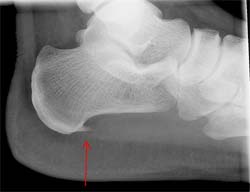

Hielspoor is een ontsteking bij de aanhechting van de peesplaat onder de voet aan het hielbeen. Eigenlijk is hielspoor een vergevorderd stadium van een peesplaatontsteking. De ontsteking is dan zo ver doorgegaan, dat er een benige uitwas is ontstaan aan de onderzijde van het hielbeen. Zie ook de röntgenfoto rechts (bron: Lucien Monfils).

Een enkele keer wordt er hielspoor gezien aan de achterzijde van de voet. Deze zit dan ter hoogte van de aanhechting van de achillespees aan het hielbeen.